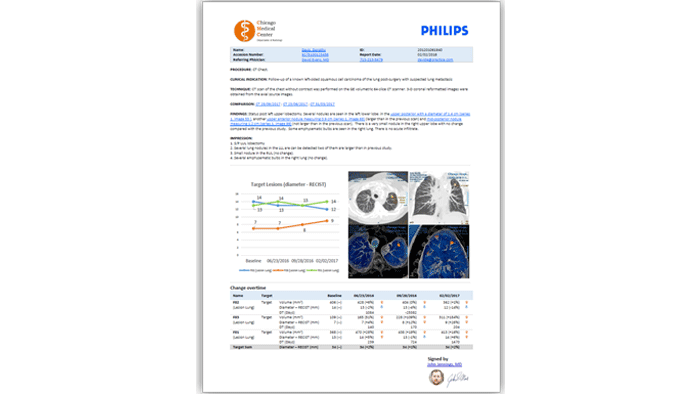

Oncology reading workflow

Providing added clinical insight to referring physicians is critical, especially for programs such as oncology. The Lesion Management Tool application allows you to offer follow-up for high-value exams requiring complex treatment planning – such as oncological exams. The Lesion Management Tool delivers the data referring oncologists need – trending analysis, measurements, anatomical bookmarking and more.

Interactive multimedia reporting

Slash your report turnaround time from days to hours. Native voice recognition, RIS and PACS integration, single sign-on and structured, user-defined reports with embedded patient data combine to take the complexity and manual entry out of diagnostic reporting.

The speed of embedded voice recognition

The Interactive Multimedia Reporting Module, with embedded voice-recognition capability, can help reduce your turnaround time. It entirely eliminates the need for typing and entry of patient or clinical context. Exam data can be inserted directly into reports. This allows radiologists to quickly review and approve final reports, while adding clinical context for referring physicians.

A single reading and reporting workspace

Reporting from any place where images can be viewed with less work and fewer errors. Simple, structured native reports enables fast evaluation and quality reporting via access to priors with hyperlinks.

Clinically rich content with smart navigation

Multimedia reports, including key images and charts for a smart and intuitive hyperlink navigation enabling value-added communication with patients. No need for special drivers or third-party software, less integration and simpler deployment during upgrades.